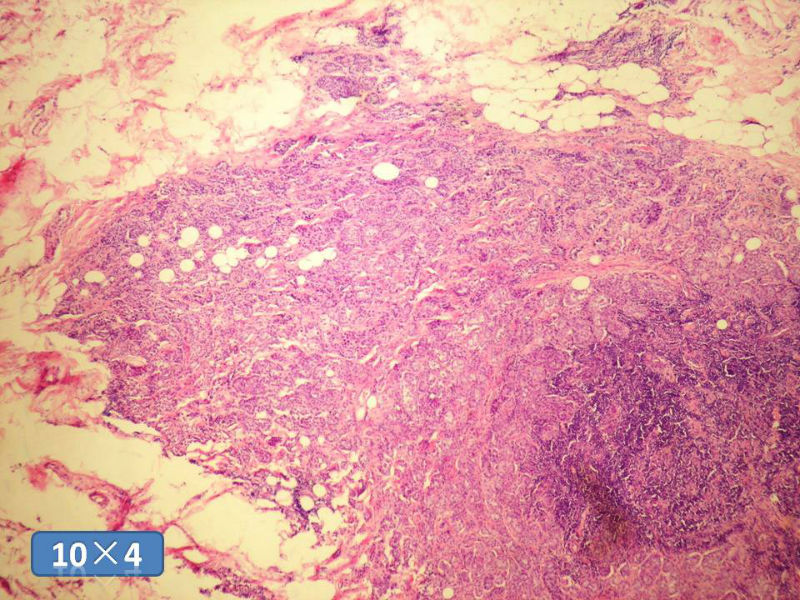

女性,50岁,乳腺肿物,冰冻切片(图1-25)

HE